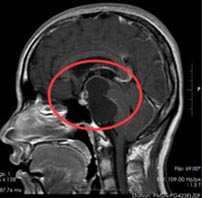

26岁的周女士,20天前出现头晕头痛症状,呈陈发性,休息也缓解不了,有加重趋势,到当地医院检查头颅MR,显示:鞍区巨大占位,考虑颅咽管瘤可能。

在广东三九脑科医院综合神经外科,经鼻蝶鞍神经内镜下行颅咽管瘤切除术,术程顺利,肿瘤全部切除。